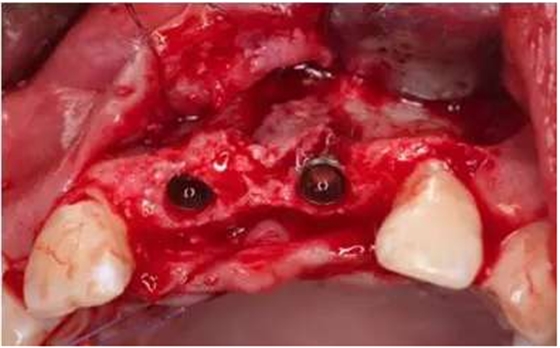

在11、21位置植入兩顆NobelActive 3.5mm*13mm種植體;

1. 近遠(yuǎn)中位置:理想修復(fù)體近遠(yuǎn)中中點(diǎn),與鄰牙牙根余留1.5mm間隙,種植體間間隔3mm以上。

2. 唇舌向位置:稍偏舌側(cè)

3. 冠根向位置:種植體平臺(tái)位于理想齦緣最高根方3mm處。

種植體頰側(cè)骨缺損處植入Bio-Oss骨替代品

覆蓋雙層Bio-Gide膠原膜